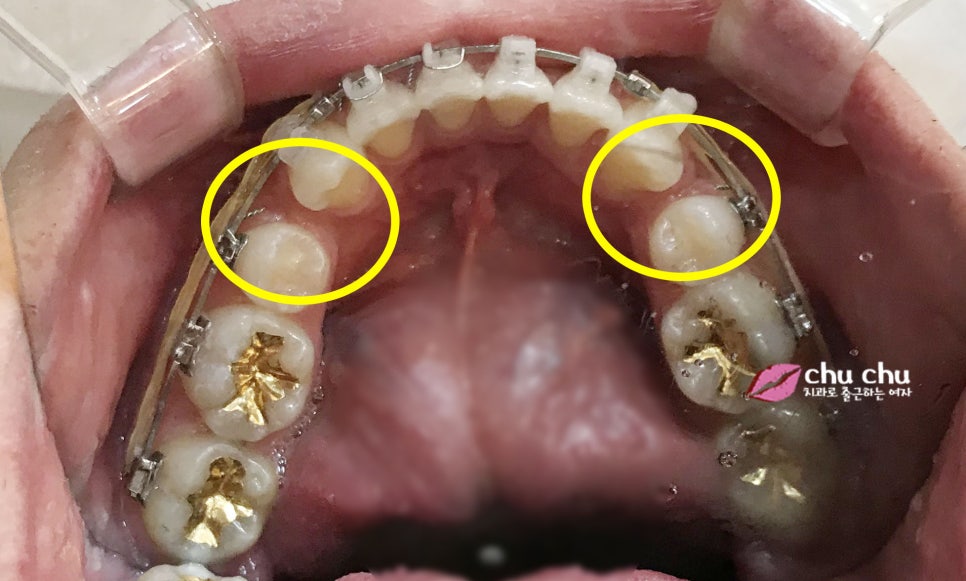

최근에 월진료 받고

바로 찍은 사진이에요!!

입매가 정말 많이 달라지셨죠??

작은어금니 발치한 공간만

파워체인으로 완벽히 쪼여주고 나면

치료가 마무리될 예정입니다~~^^

현재는 중심선도 잘 맞고

치열도 가지런히 맞춰진 상태랍니다~